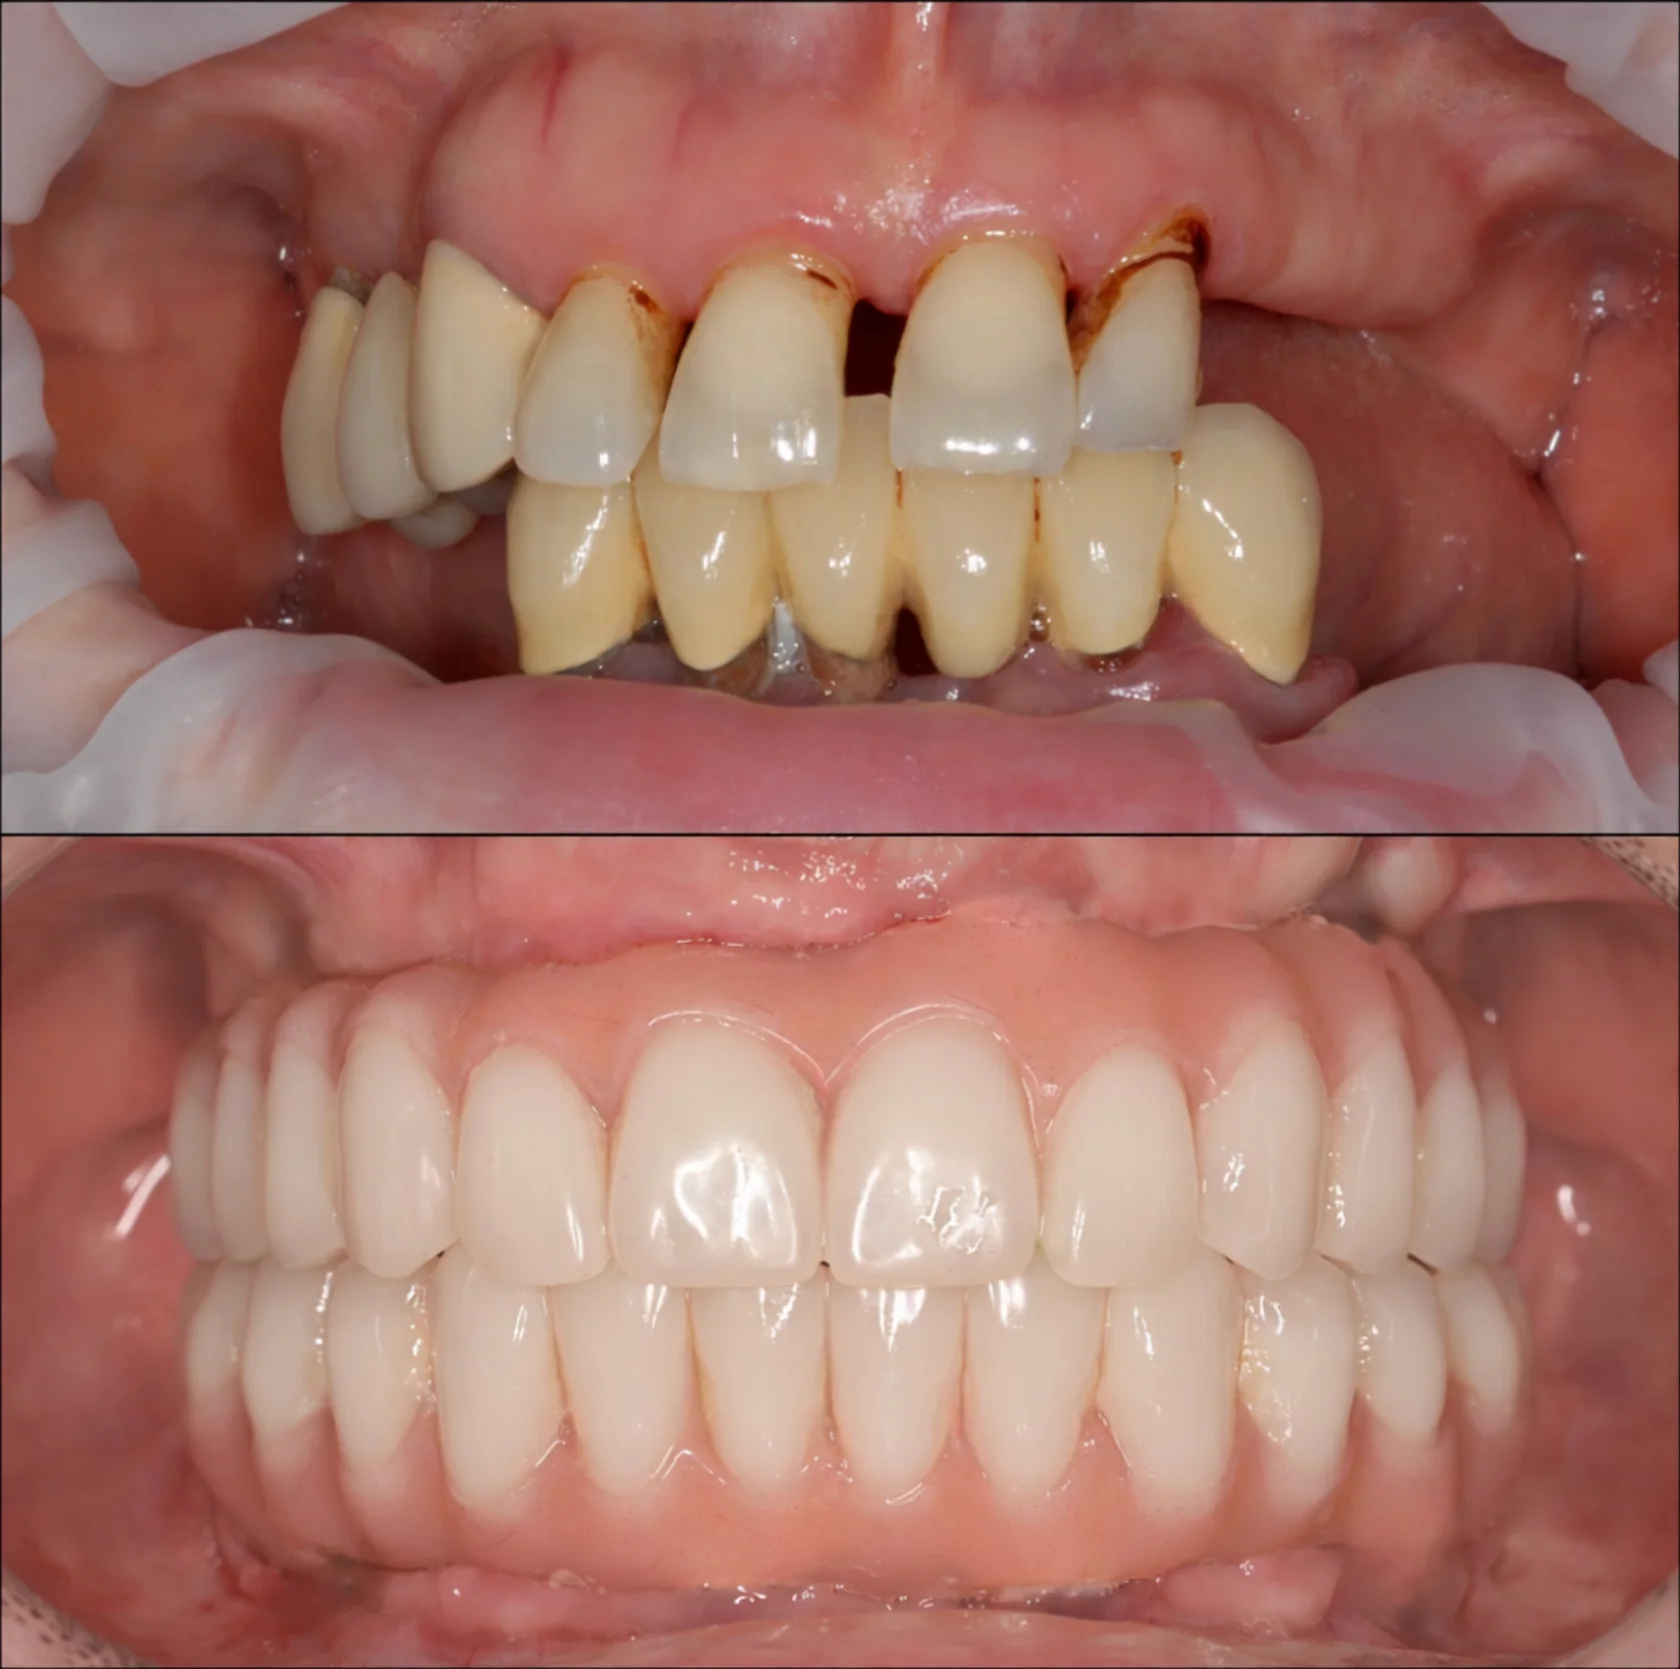

Пациент долго откладывал лечение, сомневаясь в необходимости серьёзного вмешательства и опасаясь сложной операции. Но со временем неудобства и ограничения в повседневной жизни, особенно во время приёма пищи, стали перевешивать сомнения.

На консультации мы подробно разобрали все этапы лечения, обсудили возможные риски и подобрали понятный и комфортный план. В итоге была проведена реабилитация верхней и нижней челюсти по концепции All-on-6 с немедленной нагрузкой. В день операции установлены имплантаты и несъёмные конструкции.

Сегодня пациент признаётся, что зря так долго сомневался — результат превзошёл его ожидания.

Долгое время откладывал лечение, потому что боялся сложной операции и долгого восстановления. Жил с постоянным дискомфортом и ограничениями в питании, но не решался сделать первый шаг. Длительное отсутствие зубов на верхней и нижней челюсти привело к потере жевательной эффективности и опоры мягких тканей.

На консультации мы подробно разобрали все этапы лечения, ответили на все вопросы и подобрали комфортный и безопасный план. По протоколу All-on-4 на обеих челюстях установлены несъёмные конструкции.

Уже в день операции пациент получил новую улыбку. Обеспечена стабильность прикуса, полноценная функция и выраженное улучшение лицевых пропорций за счёт восстановления опоры тканей.